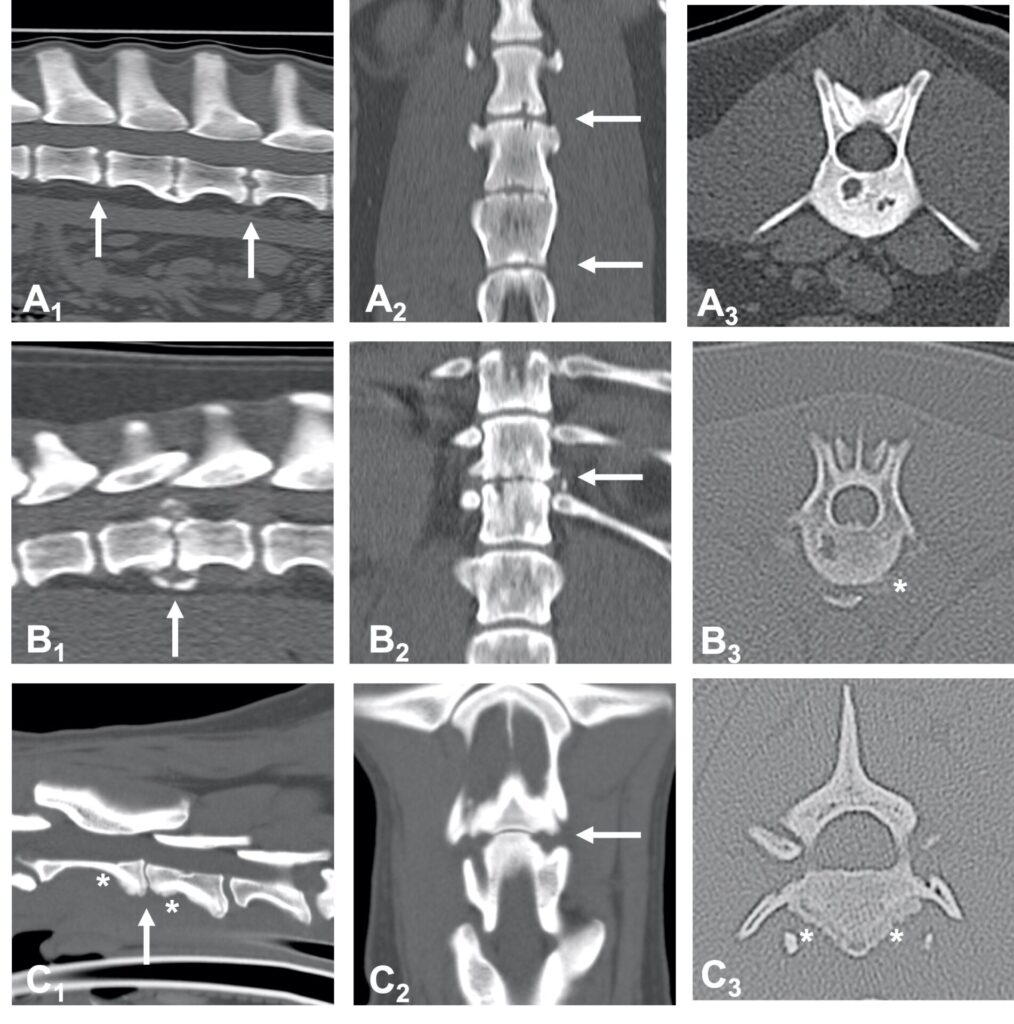

A radiograph of the spine will typically reveal damage to the vertebrae adjacent to the affected disc. The spine can become deformed and undergo bone changes as a result of chronic conditions. Radiographs may not show changes for 3-6 weeks after clinical signs begin, so if the first radiographs are normal, but the clinical signs are progressing, it is sensible to repeat them some time later.

When a typical lesion is detected, radiographs of the entire spine are recommended since some pets have multiple lesions. When a disc is infected, it degenerates and destroys the ends of adjacent vertebrae. There is evidence that these degenerative changes may weaken the vertebral column and make it more susceptible to pathologic fractures, which are caused by infection rather than trauma. As part of the healing process, the body may attempt to bridge the damaged area with bone, which may encroach on the spinal cord and nerve roots, resulting in further complications.

Imaging techniques such as computed tomography (CT) and magnetic resonance imaging (MRI) are more sensitive than plain radiography, particularly when it comes to detecting the problem early on.